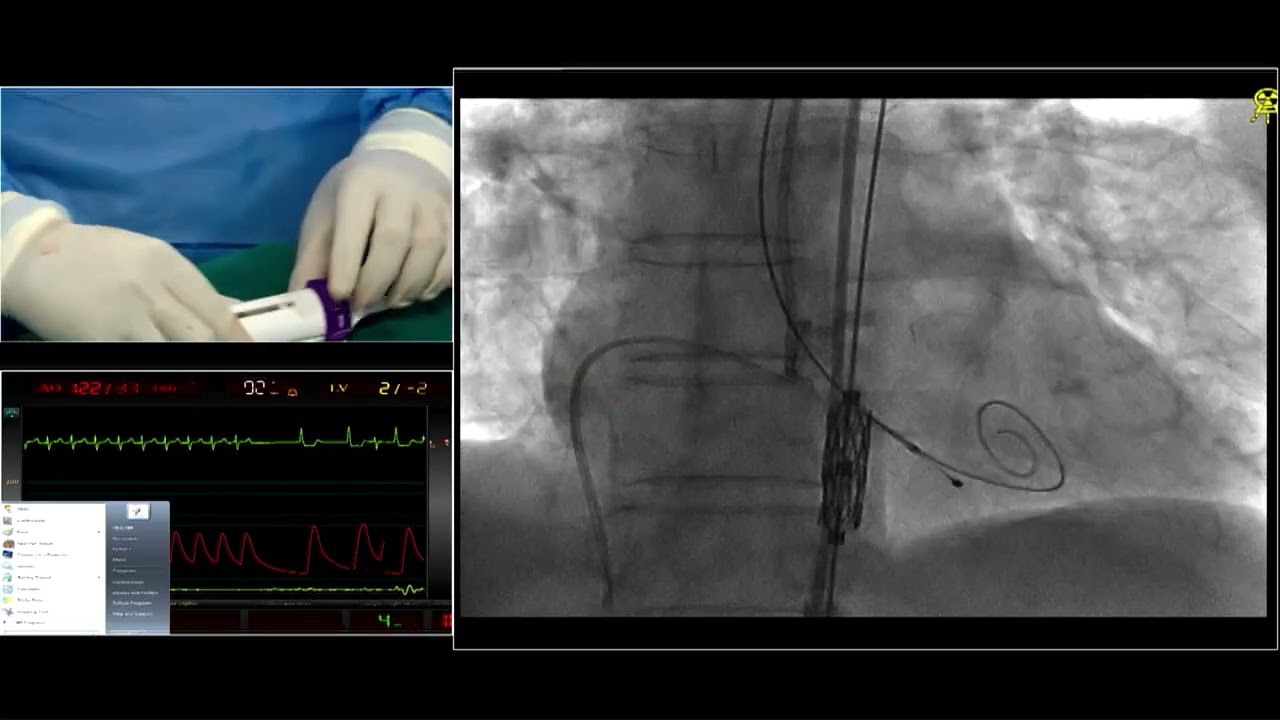

CT scan analysis in live case at EuroPCR 2024